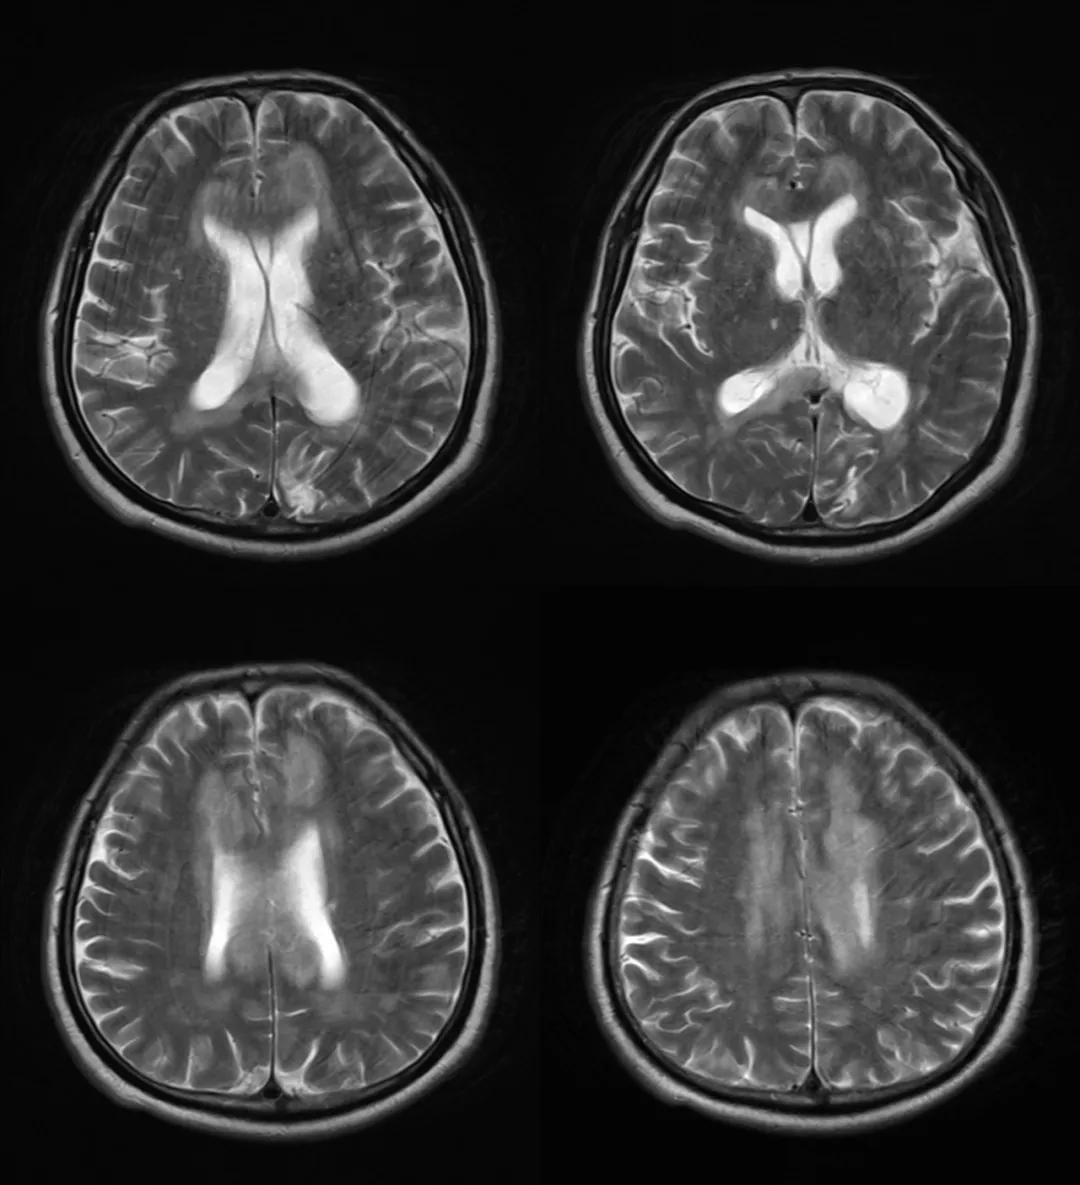

- 急性期表现为胼胝体弥漫性肿胀,T1WI呈稍低信号,T2WI及FLAIR呈稍高信号,以矢状位观察最佳,可单独累及胼胝体压部或整个胼胝体,DWI呈高信号,ADC图呈低信号,部分患者可观察到脑室周围白质或内囊受累,少见皮层受累,表现为扩散受限,不强化和强化病例均可见到。如果增强扫描可见胼胝体有不同程度强化,呈小灶状或不规则斑片状,系血脑屏障破坏所致(如本例),本例患者处于急性期。

48岁,男性,长期饮酒过量20年,出现出现眩晕,胼胝体、侧脑室周围白质、内囊后肢对称性异常信号,扩散受限,诊断为原发性胼胝体变性急性期。